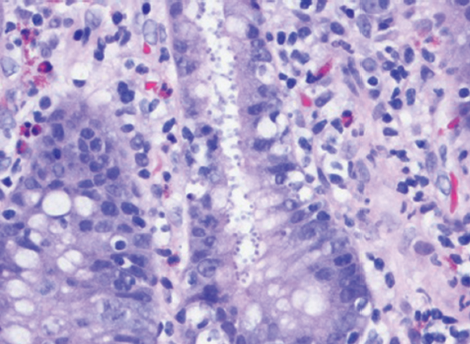

Precise identification of S schenckii requires histopathological assessment conducted with periodic-acid Schiff staining. The accepted treatment of sporotrichosis varies around the world—from potassium...